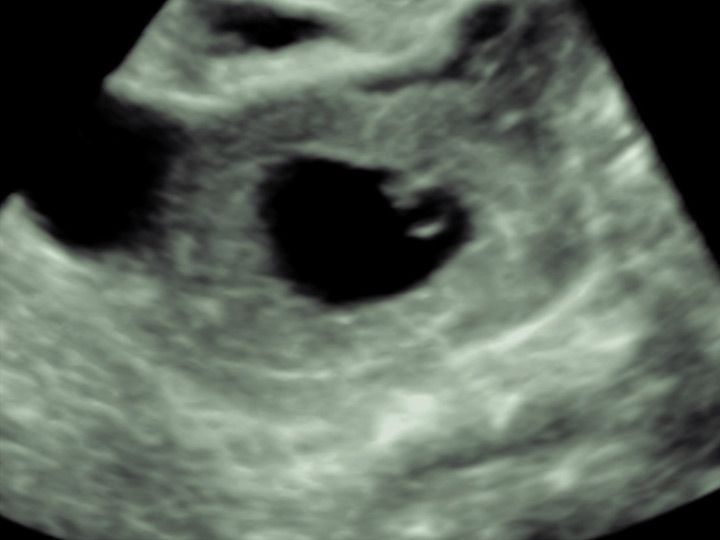

2% aller Schwangerschaft nisten sich unglücklicher Weise außerhalb der Gebärmutter ein. Hier wird dies eigentlich mit Freude erwartete Ereignis der Schwangerschaft zur mütterlichen Gefährdung ohne Aussicht auf ein Austragen der Schwangerschaft.

In der deutlichen Mehrheit der Fälle nistet sich die Schwangerschaft in solchen Fällen im Eileiter ein und kann hier bei weiterem Wachstum zur Ruptur des Eileiters und schweren Blutungen führen. Daher sollte dieses Problem erkannt werden, bevor es zu solch fortgeschrittenen Komplikationen kommt.

Eileiterschwangerschaft

Mithilfe regelmäßiger Bestimmungen des Schwangerschaftshormons und Ultraschallkontrollen soll hierbei möglichst sicher Klarheit geschaffen werden.

Die korrekte Erkennung einer Eileiterschwangerschaft gelingt unter entsprechender

Überwachung mittels Ultraschall in fast allen Fällen, bevor es zu Symptomen kommt,

so dass eine gute Sicherheit geboten werden kann und eine gezielte, meist operative Therapie im Falle des Nachweises einer Eileiterschwangerschaft eingeleitet werden kann.